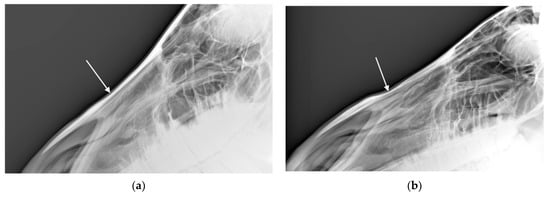

3.2.2. Radiologic Examination

Among the 144 horses, 13.8% (n = 32) had one or more radiographic changes to the mandible according to both radiologists. Another 63.9% (n = 9) had no changes detected by either radiologist. For the remaining 32 horses, the radiologists disagreed about whether a lesion(s) was present. The distribution of radiological findings in the mandibles is shown in Figure 7.

For the 32 horses where the radiologists agreed there was at least one radiographic mandible change, the radiologists agreed about the presence or absence of bone deposition in n = 22 (69%; see Figure 8), the presence or absence of loss of bone homogeneity in n = 25 (78%, see Figure 9), the presence or absence of bone thinning in n = 30 (94%), and the presence or absence of soft tissue swelling in n = 18 (56%). An example of a radiograph showing both bone thinning and bone deposition is shown in Figure 10.

(1) Bone Deposition

Bone deposition in the mandible was noted on the radiographs of between 18.8% (n = 27) and 32.6% (n = 47) of the 144 horses. For the majority of these horses (n = 19–41), the noted change was mild and changes in no horses were considered marked by either scorer. Agreement was moderately good with a percentage agreement = 79.9% and a square weighted Cohen’s kappa = 0.764 (z = 9.41, p < 0.001).

Figure 8. Radiograph showing the mandible of a horse in which radiologists (n = 2) agreed there was bone deposition that was: (a) typical of affected horses and (b) moderate.